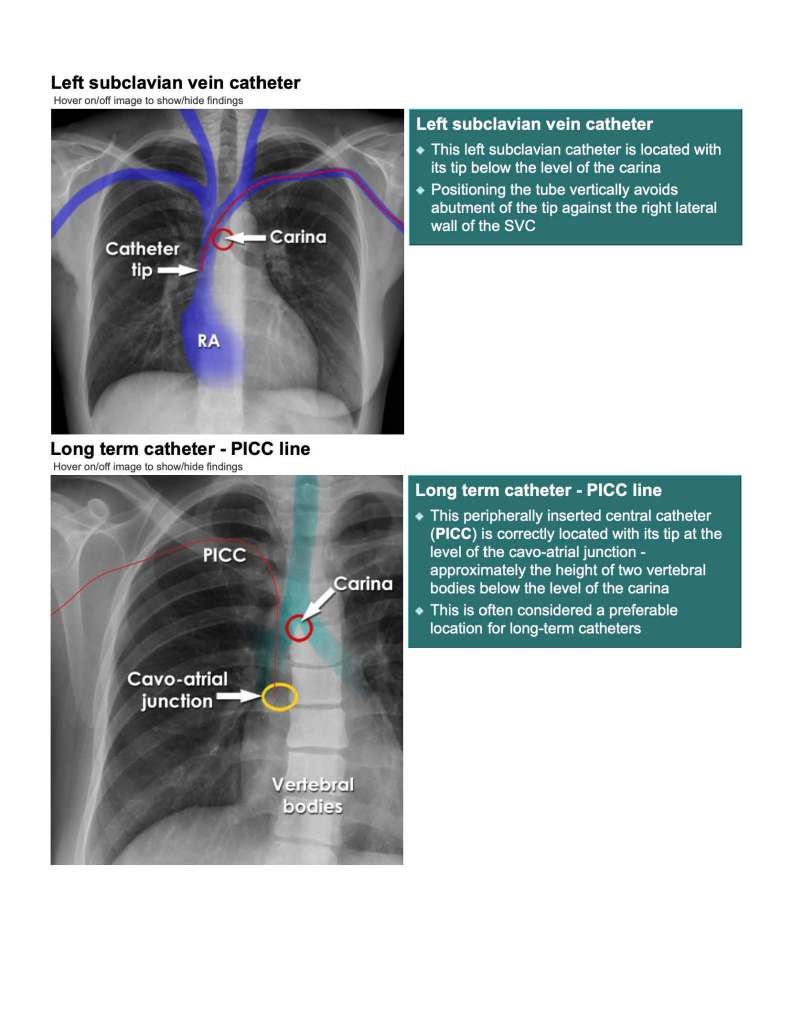

Central Line Leave a reply Here is a summary of some pearls from EMCRIT’s videos on central line placement. summary-of-emcrit-central-line-procedure-1Download Share this: Share on X (Opens in new window) X Share on Facebook (Opens in new window) Facebook Like Loading... Related